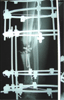

Post Op

SURGICAL TREATMENT

▪ 28/4/1999

▪ Sequestrectomy (5 cm bone block removed)

▪ Gentamicin beats

▪ Trifocal Ilizarov bone transport and compression

▪ 5 Ilizarov ring configuration

▪ IM tibia guide wire inserted |